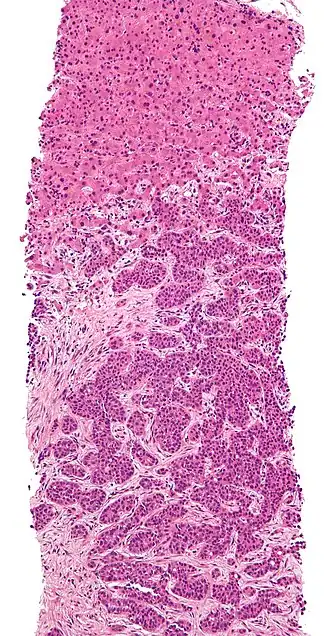

Metastatic disease to the liver

Metastatic disease to the liver